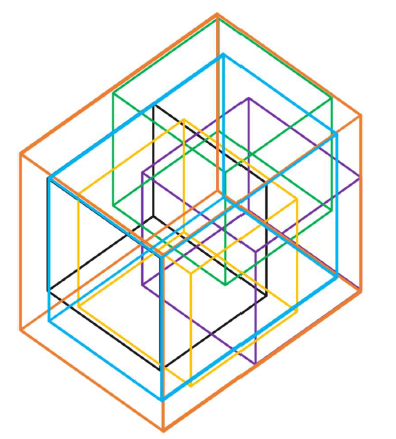

Following the procedure outlined in section 3.2.6, the candidate bounding boxes were fused together to generate an all-encompassing bounding box shown in orange in Figure 11. This bounding box is fine-tuned by moving the boundary walls towards the centre by an offset value, shown in blue in Figure 11. This offset factor is a percentage of the difference between the lowest and highest values of the lower bounds of individual bounding boxes. In Figure 12, a plot of the average IOU values against offset values is shown for each of the five fold cross validation results for localisation of the left and right kidneys. While the performance with zero offset is good with an IOU of 68% (with values of IOU above 33% (DC 50%) considered acceptable), an optimal value is achieved for an offset value of 33%. This value was found to hold good for lumbar spine and spleen as well and therefore was used as a criterion for fusing bounding boxes.